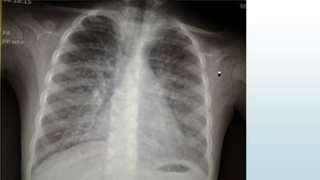

تشخيص :

Pulmonary Alveolar Microlithiasis